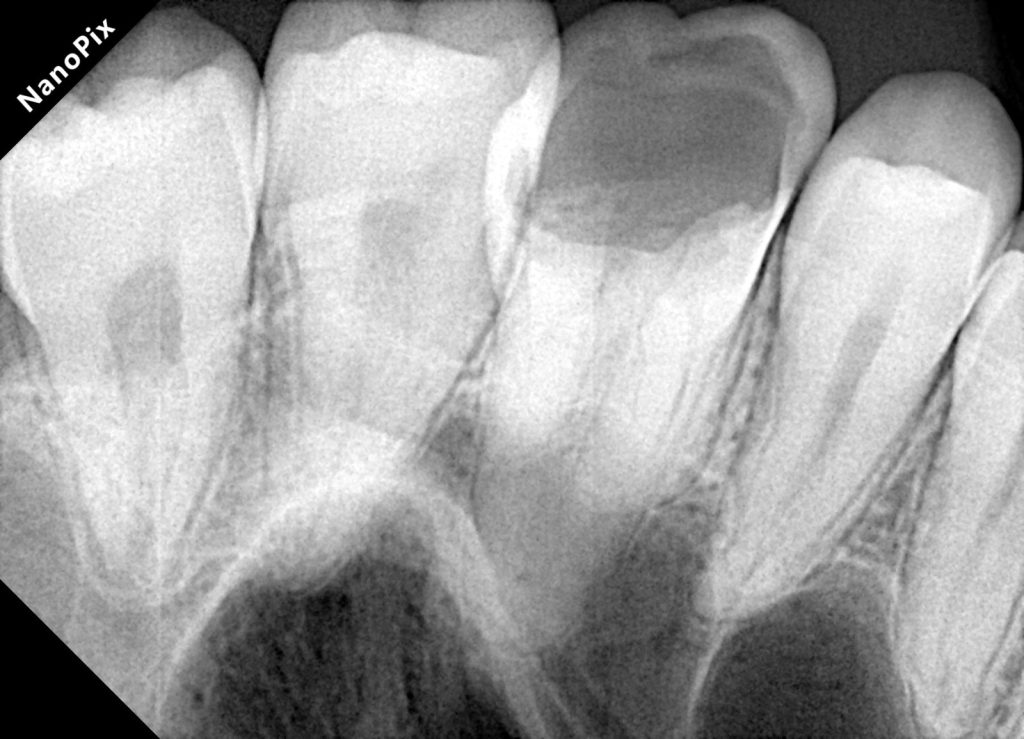

4. CORE BUILDUP & INTERNAL REINFORCEMENT

Composite Build-Up

A controlled build-up was done using:

- 3M Easy Match Shades for dentin & enamel

- Natural saturation using Tokuyama Estelite Ocher Stain for warmth

Fiber Reinforcement (If required)

EverX Posterior or Ribbond may be used in cases with thin cusps for internal support.

5. PREPARATION FOR COMPOSITE ONLAY

Minimal preparation was done:

- 1.5–2 mm reduction of functional cusps

- Smooth, rounded internal angles

- Supragingival margins after DME

- No unnecessary removal of sound enamel

Onlay preparations are ideal because they preserve enamel, improving bond strength and tooth longevity.